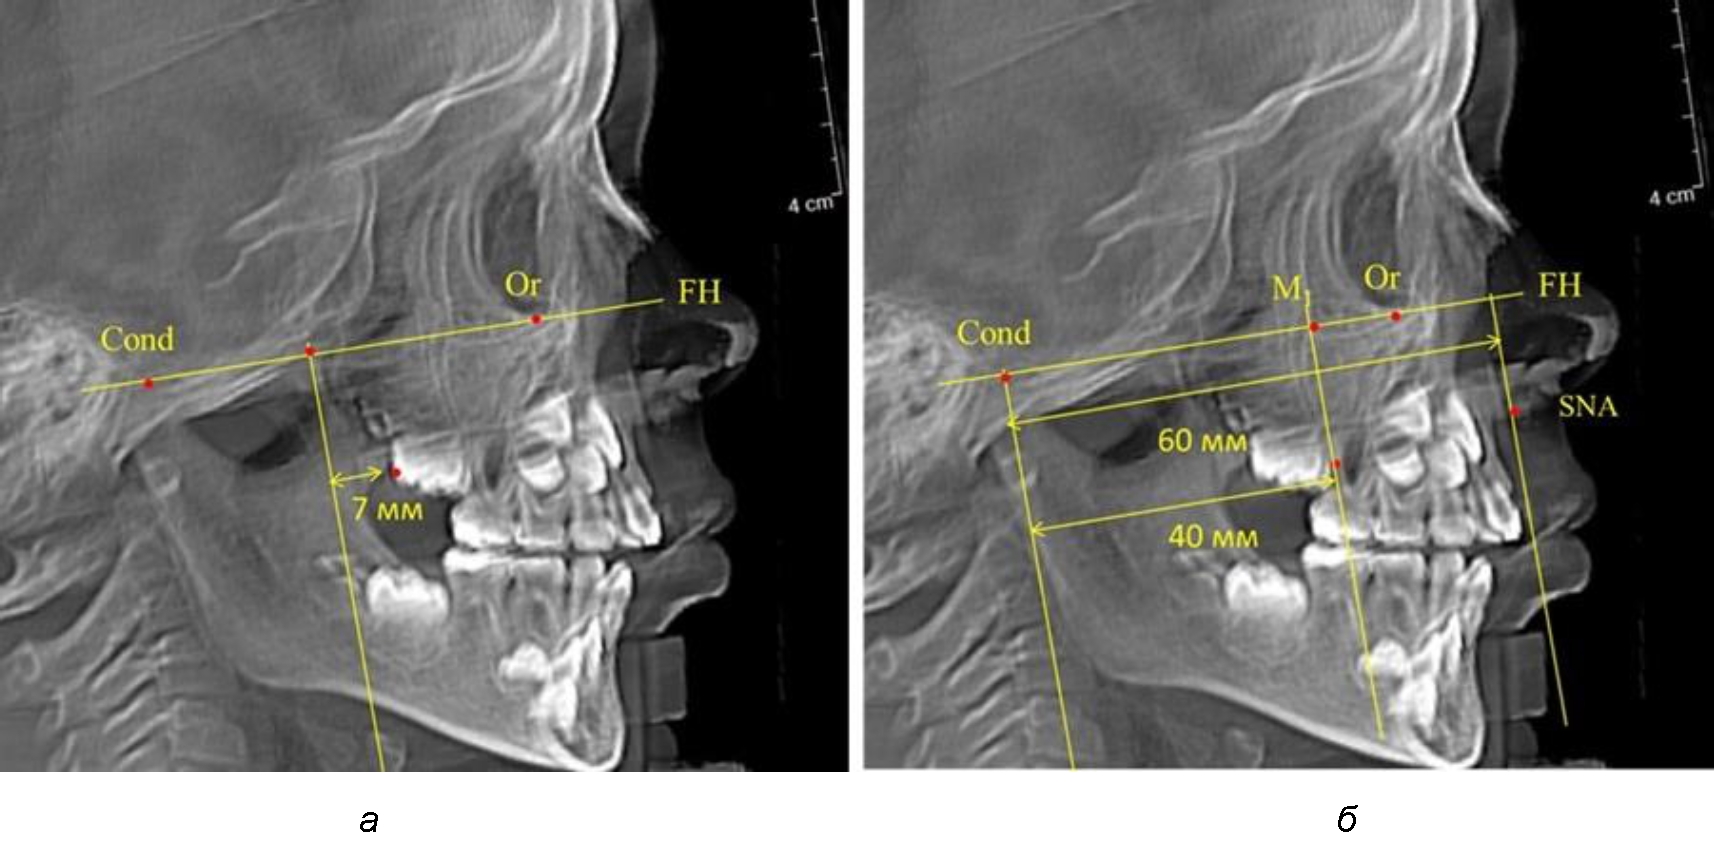

Так, при расстоянии от крыловидной вертикальной плоскости PTV до дистальной поверхности верхнего первого постоянного моляра в 13 мм сагиттальный размер гнатического отдела был 82 мм. При этом отношение кондилярно-спинального расстояния к кондилярно-молярному размеру (54,5) было близким к коэффициенту 1,5, что представлено на рис. 2.

Рис. 2. Особенности положения первых моляров по R. E. McDonald (а) и по предложенному методу (б) при уменьшенном молярно-крыловидном расстоянии

Второй частью исследования был анализ положения первых постоянных моляров в различные периоды сменного прикуса. На телерентгенограммах детей периода прикуса молочных зубов дистальная поверхность зачатка первого постоянного моляра отстояла от крыловидной вертикали на величину, составляющую около 7 мм, что было близким по значению к данным R. E. McDonald. Сагиттальный размер гантического отдела составлял около 60 мм, а его отношение к кондилярно-молярной глубине – 1,5 (рис. 4).